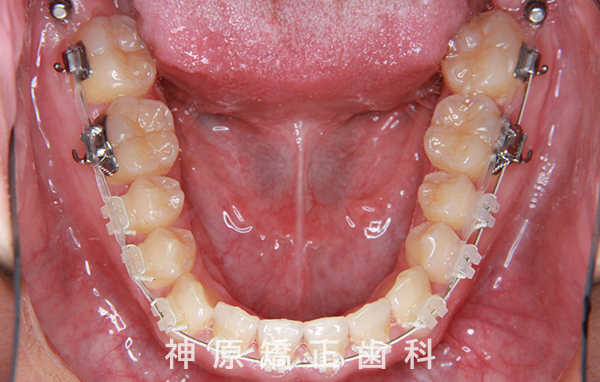

マルチブラケット装着1年後

- 治療に用いた主な装置

-

上顎:リンガル(舌側)矯正装置

下顎:唇側矯正装置

歯科矯正用アンカースクリュー - 抜歯 / 非抜歯

- 小臼歯非抜歯治療、上下左右親知らず抜歯